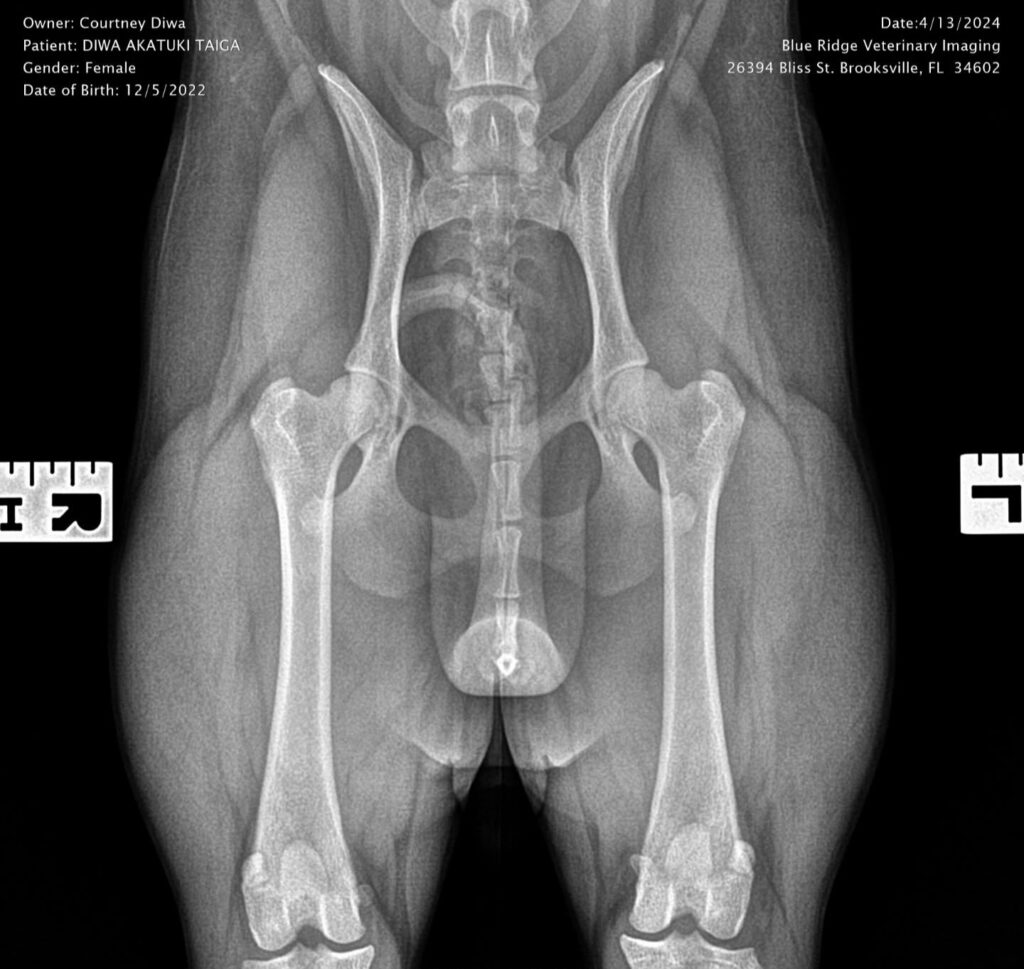

Titles & Health Certificates